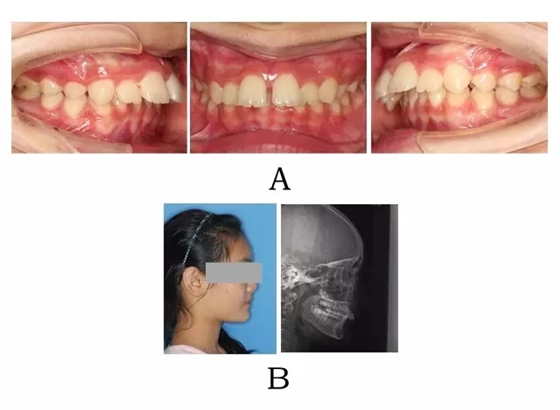

面型前突,唇態(tài)較正常,而下部高度不足、頦唇溝較深,下頜平面較平坦??趦?nèi)表現(xiàn)上頜正?;虬檩p度齒槽性前突,上前牙輕度唇傾。下頜后退,嚴(yán)重的深覆合深覆蓋,磨牙關(guān)系常為遠(yuǎn)中關(guān)系,尖-尖咬合(圖3-1)。

圖3-1:頜位性突面畸形臨床表現(xiàn)及頭顱側(cè)位影像特征。

(A)齒槽與牙列特點(diǎn) (B)側(cè)貌與影像對(duì)比

Figure 3-1. Clinical manifestation and cephalometric image for mandibular positional prognathism. (A) Alveolar and dentition specifics. (B) Facial profile and radiographic image.